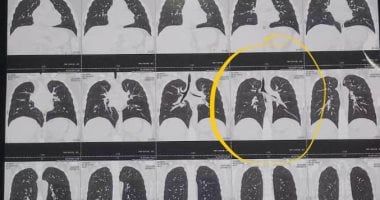

وأضاف: بعد مرور عدة أيام شعر الطفل بعدم ارتياح وزيادة الكحة وظهور صوت من صدره مع التنفس، مبينا أنه استقبل الطفل واستمع من أسرته حول تاريخه المرضي وطلب منهم إجراء اشعة مقطعية علي الصدر للاطمئنان وتبين وجودها في الفص السفلي للشعبى اليسرى وقرر الفور إجراء منظار شعبي صلب تحت التخدير الكلي، بمشاركة الدكتور سامح فتحي أستاذ التخدير بكلية الطب جامعة طنطا، وتم إخراجها في عملية لم تستغرق أكثر من 5 دقائق، مشيرا إلى أنها لم تسبب انسدادا كليا في الشعب الهوائية ولم يتم اكتشافها مبكرا بسبب صعوبة التشخيص وقتها.

ظهور غطاء القلم في الأشعة المقطعية